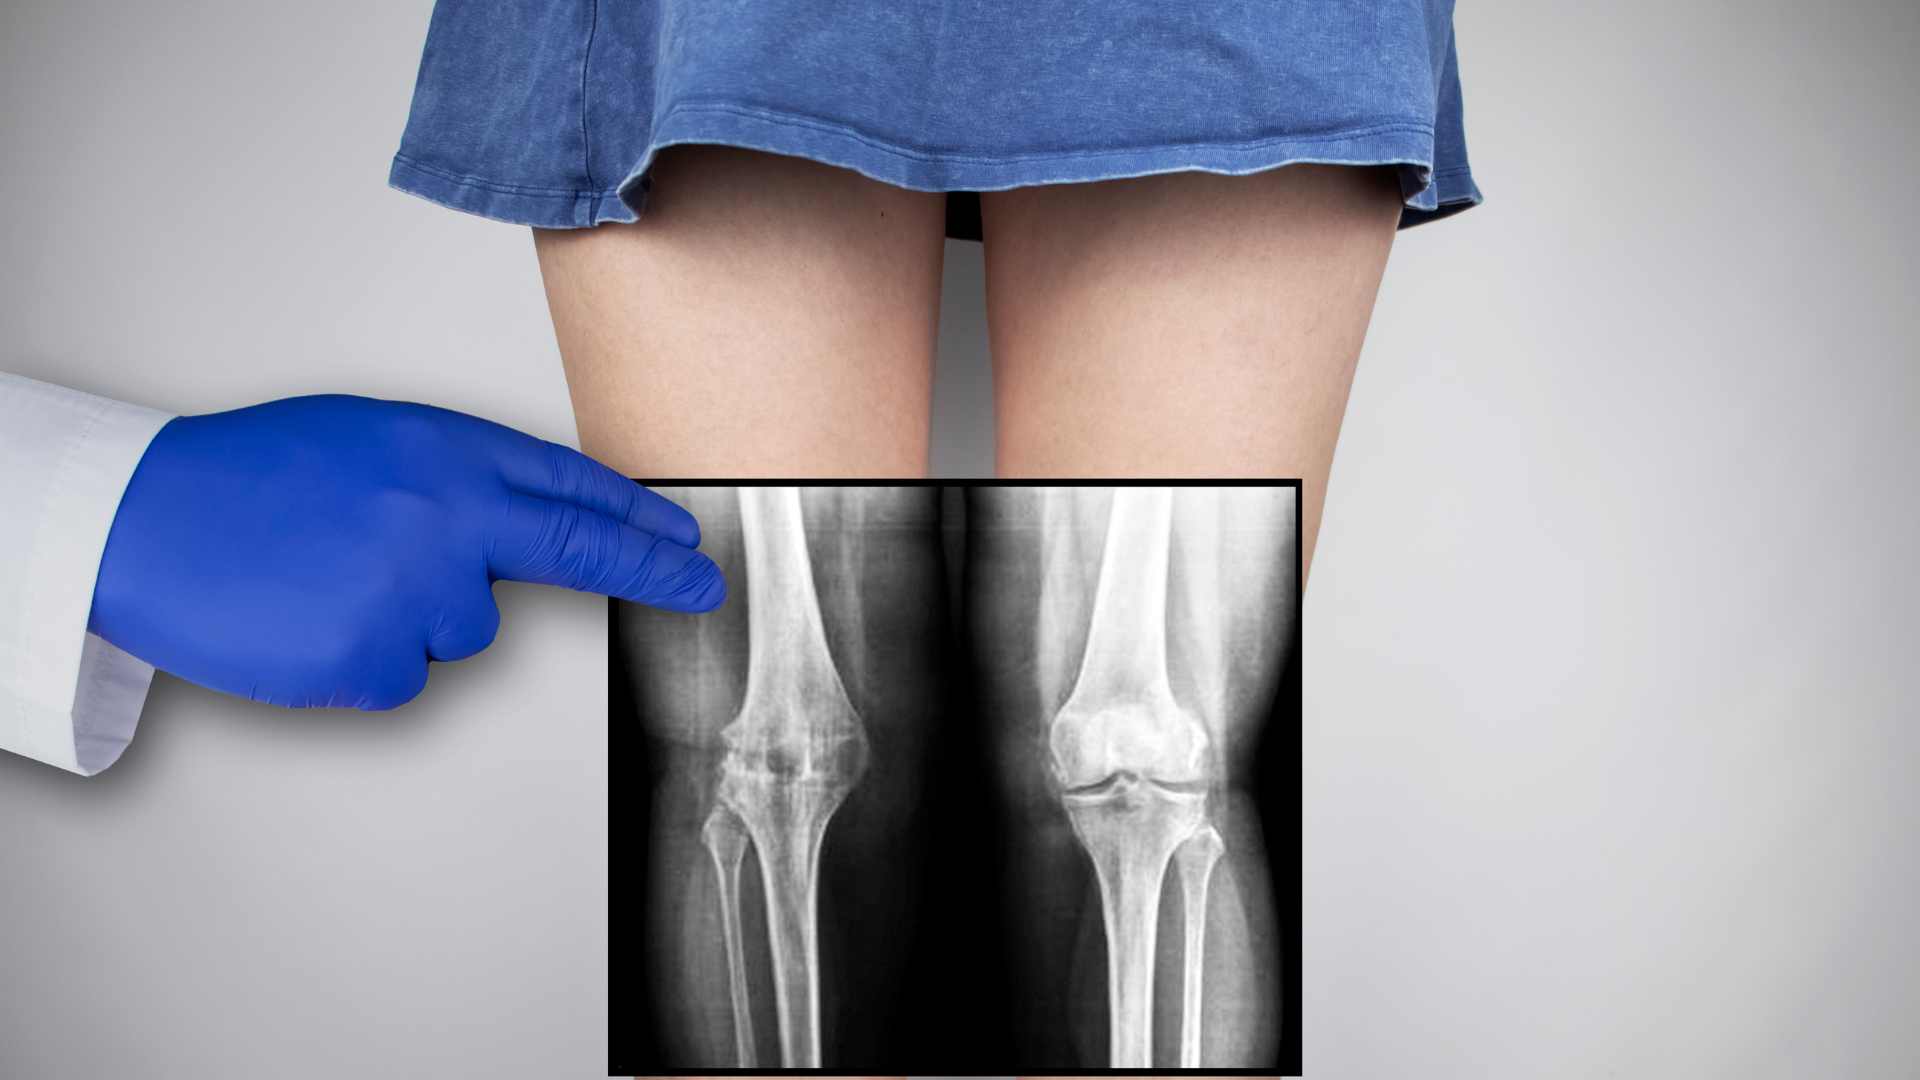

Chân vòng kiềng là tình trạng hai chân không duỗi thẳng, đầu gối cong vào trong hoặc ra ngoài. Biến dạng này thường gặp hai dạng. Chân chữ O là khi đầu gối hướng vào trong, tạo khoảng cách giữa hai gối ngay cả khi đứng khép chân. Ngược lại, chân chữ X là tình trạng đầu gối hướng ra ngoài, khiến hai cổ chân khó chạm vào nhau.

Biến dạng này không chỉ ảnh hưởng đến dáng vóc mà còn gây hại cho khớp gối. “Khi chân bị cong, khe khớp hẹp lại, lực dồn nhiều hơn khiến khớp dễ bị đau và thoái hóa sớm”, bác sĩ chỉnh hình Kim Sang-beom (Bệnh viện Sunsoochon, Hàn Quốc) cho biết.